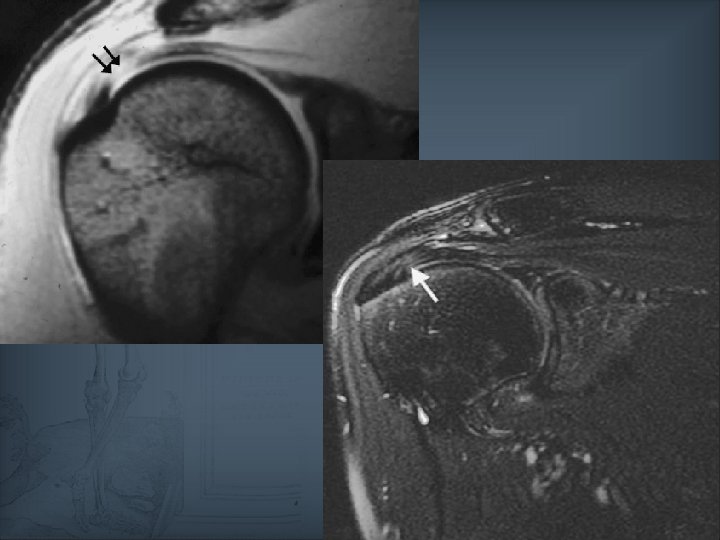

Pathologie de coiffe Sémiologie : Hypersignal T 2 liquidien intra-tendineux et aspect morphologique évocateur = rupture Hypersignal T 2 non liquidien : tendinopathie Hypersignal T 2 liquidien d’allure strictement intratendineux : possibilité de dégénérescence mucoïde interstitielle Limite : exceptionnellement, la rupture peut présenter un hyposignal T 2 (13%) – mais anomalie morphologique du tendon toujours présente, voire rétraction Préférer le T 2 au DP pour s’affranchir de l’artefact de l’angle magique (TE courts)

Quand évoquer une rupture de la coiffe ? Kyste intra-musculaire (1% des cas mais Sp+++) Double épanchement pour son caractère transfixiant (VPP de 54 à 95%) Anomalie de signal venant au contact d’une surface

Pathologie de coiffe : performances de l’IRM conventionnelle Ruptures transfixiantes : Se = 80 à 100% Sp = 94 à 99% Ruptures non transfixiantes : Se = 50 à 89% Sp = 75 à 99%